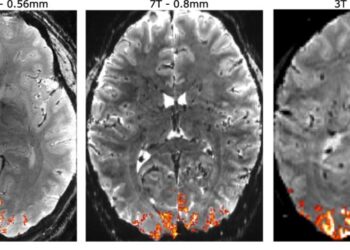

Todos los secretos que esconde la mente de los psicópatas

Con una resolución más alta, los neurocientíficos pueden localizar de manera más precisa las señales (naranja) en el cerebro para...